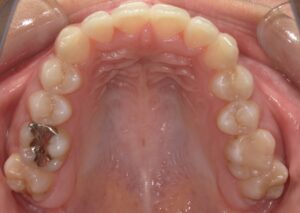

さて実際の症例です。前歯の歯並びを主訴にいらっしゃった方です。

前歯の歯並びが気になるとの主訴でご来院頂いた患者さんです。

前歯の出っ歯傾向があるのがわかります。矯正方法(ワイヤー矯正、インビザライン矯正)、抜歯の必要性や期間費用をご説明しワイヤー矯正で治療を進めていくこととなりました。

2年後の歯列矯正後の写真です。

上の前歯の出っ張りがなくなり綺麗な歯並びになっているのが分かります。その後、金具が装着されていたボンドを除去しホワイトニングを行い歯の更なる審美改善を行いました。